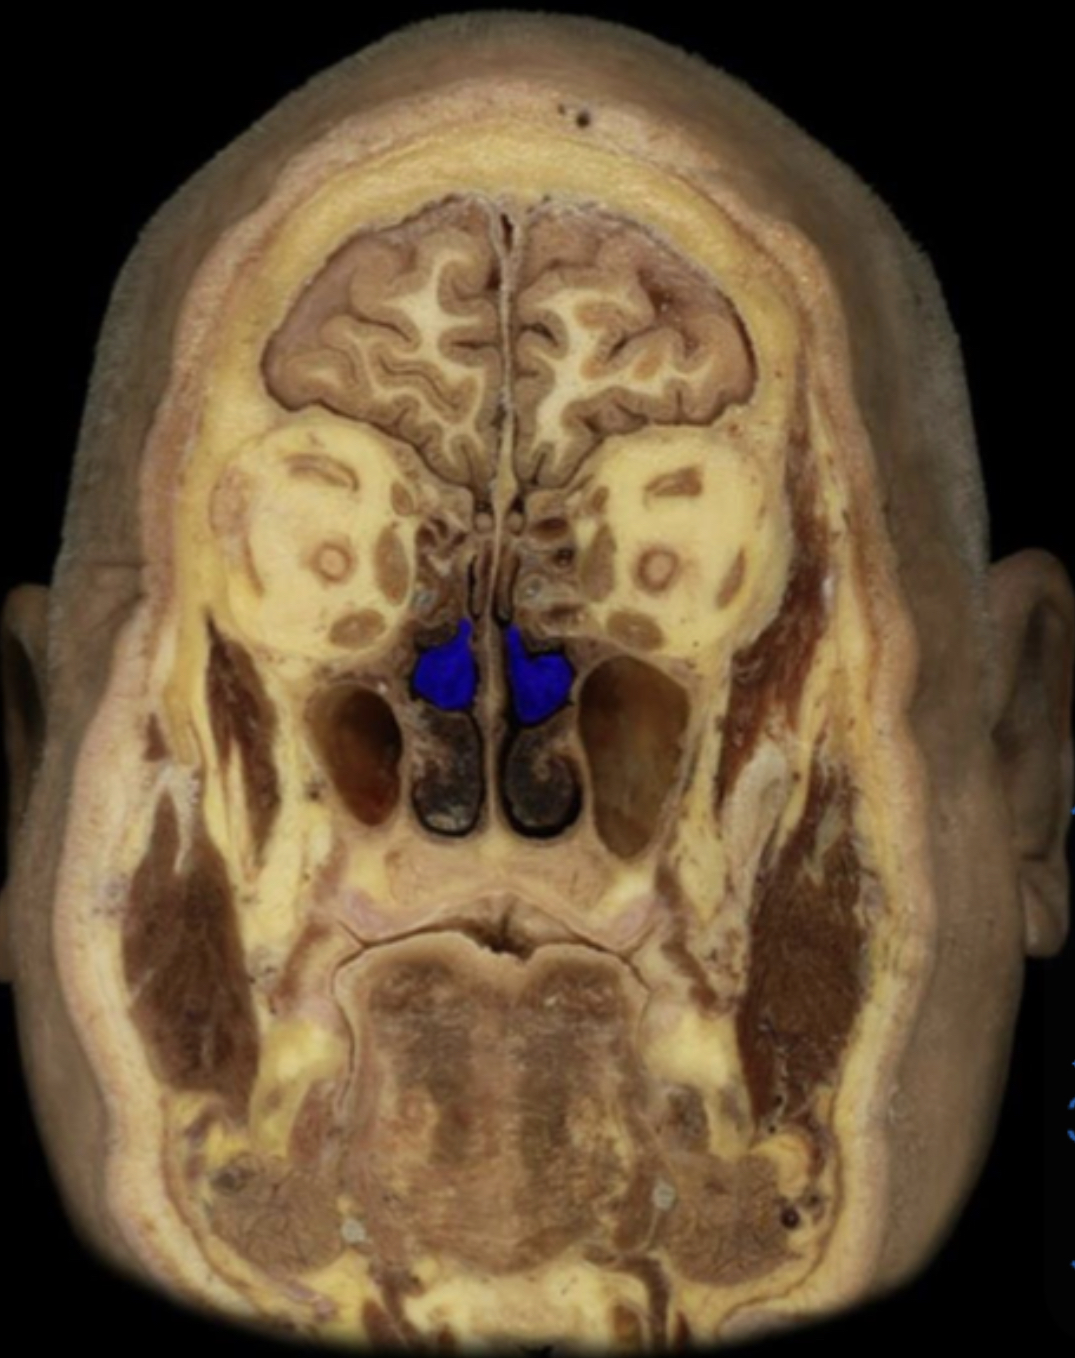

Maxillary sinus

What structure is highlighted in blue?

Middle nasal concha

Middle nasal meatusย

Nasal cavity

Nasal septum